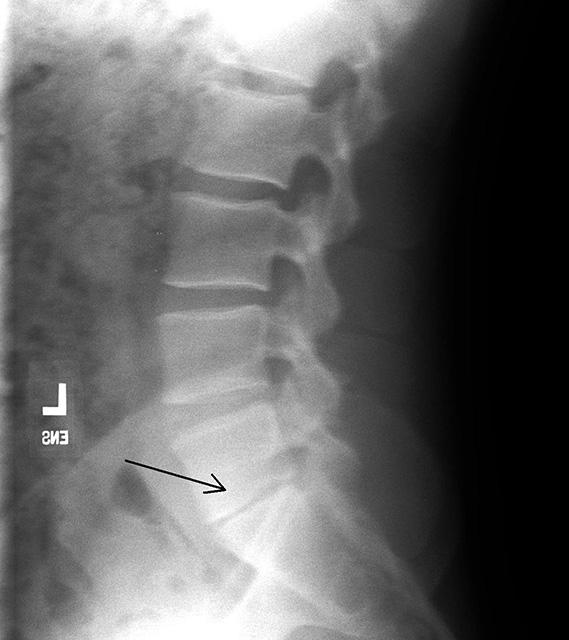

slipped disc lumbar x ray – Bernadette Slater

Assesment of the x-ray features of lumbar disc degeneration-lateral …

Disc space narrowing and degenerative changes at the L3-L4 level …